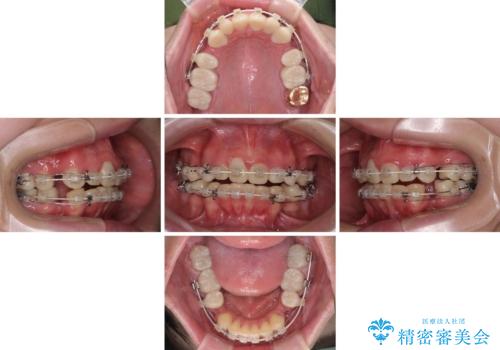

- 一時期の拒食症に伴い歯が酸で溶けてボロボロになってしまったとのことで来院された患者様です。

酸によりエナメル質の大半が溶けており、下顎前歯以外は酷いむし歯のような状態でした。

当初はほとんどの歯をむし歯治療のようにオールセラミッククラウンにて補綴治療を行う予定でしたが、仮歯に置き換えた時点で、口元の突出感や下顎前歯の叢生が気になるとのことで、上下左右の第一小臼歯4本を抜歯したワイヤー装置での抜歯矯正を行うこととしました。

矯正治療終了後に、残った歯をオールセラミッククラウンにて補綴治療を行うこととしました。